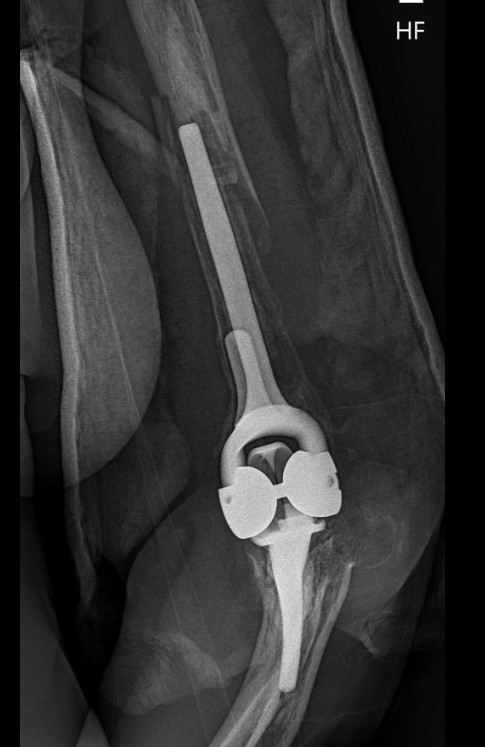

Coonrad-Morrey Discovery Elbow Latitude

Arthroplasty

4. Trial reduction

5. Insert cement restrictors / implant ulna and humeral prosthesis

6. Insert bone graft under anterior flange

7. Link components

8. Repair collaterals if needed